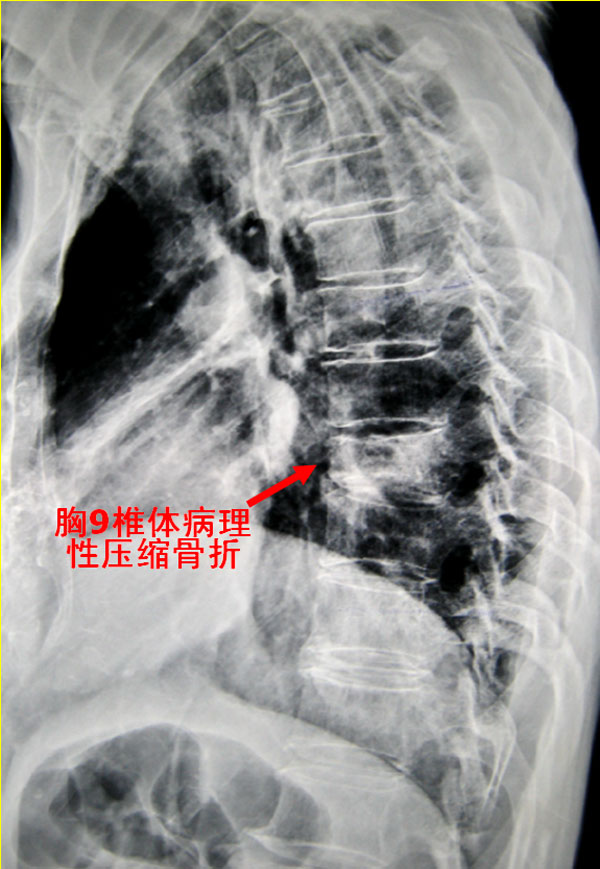

该男性患者现年73岁,自述其反复胸背部疼痛约8个多月,病情加重1周后入院。瑞康医院骨脊柱科专家为其检查身体发现,其胸背部有压痛、叩击痛。患者的胸椎X光片显示其胸9椎体有病理性压缩骨折(图1),胸椎CT片显示其椎体破坏(图2),胸椎MRI检查显示其胸9椎体及椎弓呈现长T1异常信号改变(即肿瘤样改变),椎体后缘突入椎管,导致脊髓受压,增强MRI可见病灶强化影(图3)。前列腺MRI提示该患者患前列腺癌的可能性较大。

胸9椎体病理性压缩骨折